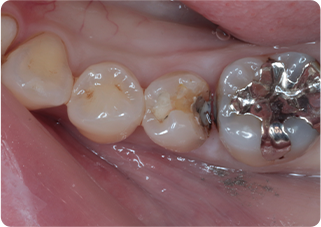

精密根管治療④

術前

術後

| 主訴 | 奥歯で噛むと痛い |

| 治療期間/回数 | 1ヵ月、3回 |

| 価格(税込) | 88,000円(税込) |

| リスク・副作用 | 病変再発、歯根破折の可能性 |

| ポイント | う蝕検知液を用い、むし歯の取り残しが無いようにし、ラバーダム防湿を行い、無菌的に根管治療を行った。根管充填材は、殺菌作用の強い保険適応外のMTAセメントを使用した。 |